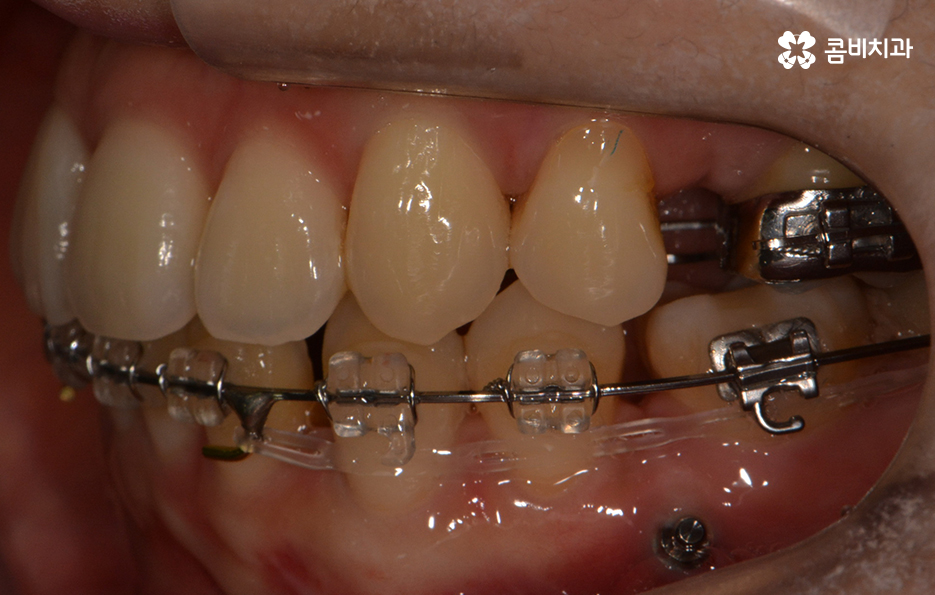

발치가 진행되었고 콤비교정 장치를 사용하여 교정이 진행된 사례

콤비교정은 윗니는 설측으로 장치가 부착되며 아랫니는 순측으로

치아 바깥쪽에 장치가 부착되는데요.

평상시 대화를 하고 웃을 때 윗니가 위주로 보이기 때문에

크게 웃지 않는 이상 일상생활을 하실 때

교정 사실이 거의 드러나지 않을 정도로 높은 심미성을 갖고 있습니다.